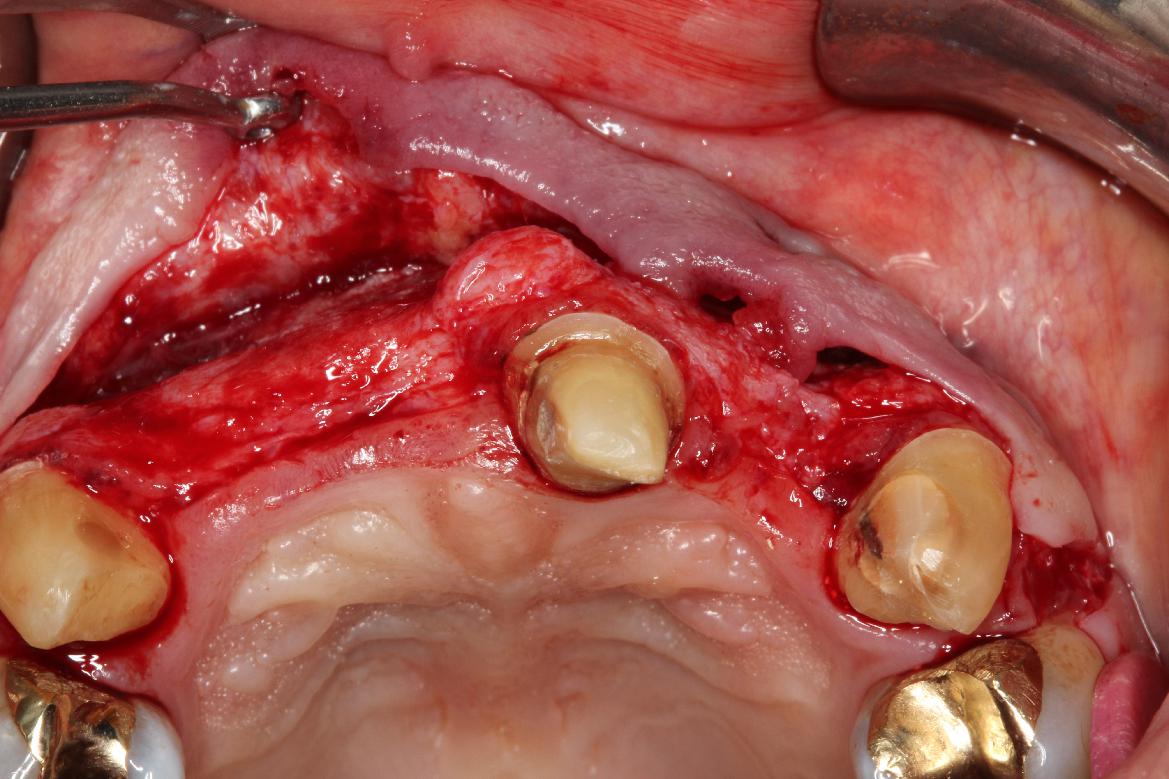

3/5 - Rehydration of mucoderm® and vertical soft tissue thickeningPre-prosthetic soft tissue augmentation of the ridge contour with mucoderm®- Dr. F. Rathe